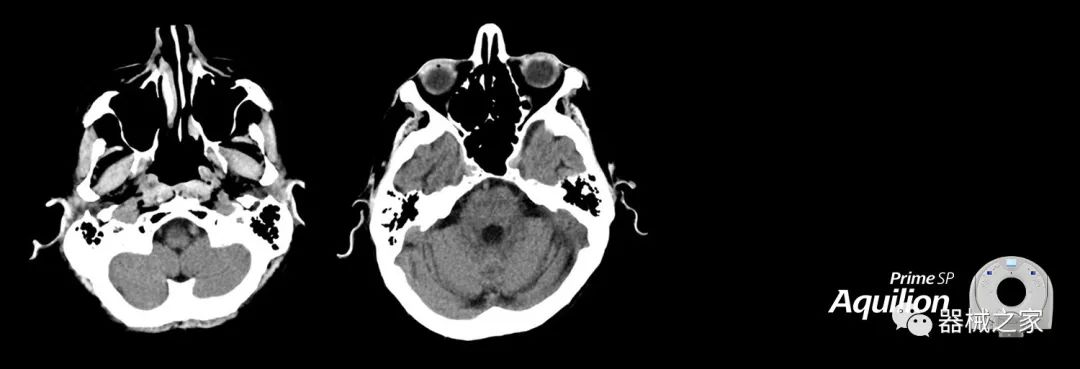

在以患者為中心的放射腫瘤學領域,計算機斷層掃描(CT)的可訪問性,可重復性和靈活性至關重要。為了建立這些價值,佳能醫(yī)療系統(tǒng)美國公司現(xiàn)在正在擴大其放射腫瘤學CT模擬產品,包括Aquilion Prime SP和Aquilion Lightning 80高級CT系統(tǒng)。除了Aquilion LB之外,Aquilion Prime SP和Aquilion Lightning 80現(xiàn)在還包括放射治療(RT)選項,可為腫瘤學規(guī)劃提供高質量的CT成像和精密工具。

Aquilion Prime SP使設施能夠處理具有挑戰(zhàn)性的案例,同時為員工提供快速,靈活和高效的解決方案。

佳能醫(yī)療的Aquilion Lightning 80掃描儀還以緊湊,經濟的包裝提供高質量的成像。Aquilion Lightning 80旨在可靠,高效地運行,在繁忙的環(huán)境中生成高質量的圖像。

兩個CT系統(tǒng)均采用0.5 mm x 80排PUREViSION探測器技術(可配置并從80-160現(xiàn)場升級),78 cm孔徑,50 cm視野,AIDR(自適應迭代劑量減少)3-D和SEMAR(單個)能量金屬神器減少)技術。